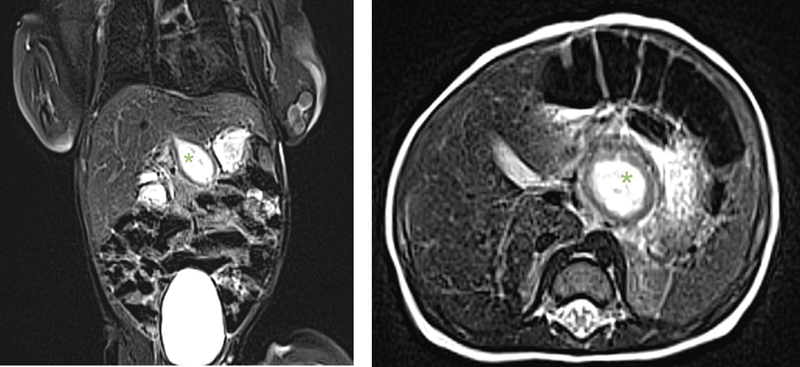

Accessory liver lobes are rare. We present the rare case of torsion of an accessory liver lobe in a neonate. A 13-day-old newborn presented with failure to thrive and hematemesis without fever. The initial workup with sonography, magnetic resonance imaging, and upper gastrointestinal study was suspicious of a duplication cyst, most likely in the posterior wall of the stomach. Laboratory and radiological findings were not suggesting a choledochal cyst. We performed a laparotomy with resection of the 3.2 × 2.1 × 1.1 cm mass. Intraoperatively, the cystic formation extended from of the liver bed up to the lesser curvature of the stomach. The mass was attached to the left liver lobe with fibrous bands. Histopathology revealed necrotic liver parenchyma with patent viable biliary ducts, indicative of an accessory liver lobe that underwent torsion in the perinatal period. The postoperative course and follow-up (6 months so far) were uneventful. To our knowledge, this is the youngest described patient in the literature with an accessory liver lobe torsion and the second case report concerning this entity in a neonate. It presents an extremely rare differential diagnosis in symptomatic neonates with a cystic mass in the upper abdomen.